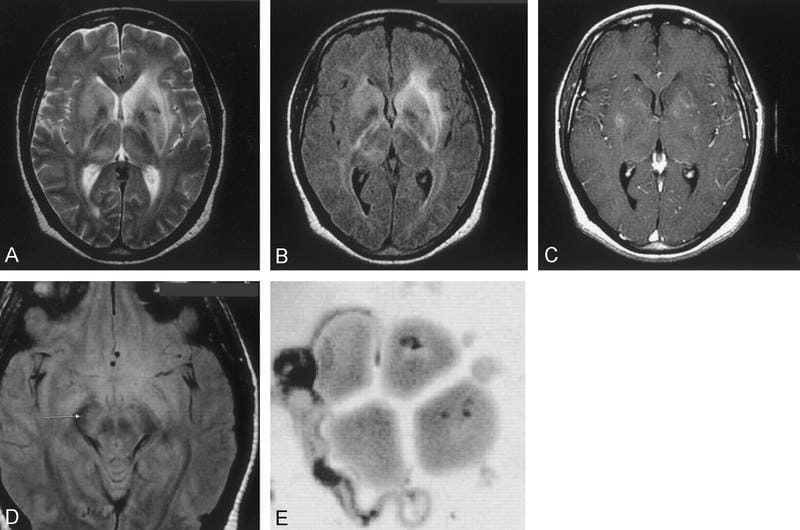

Image of the disease African Trypanosomiasis